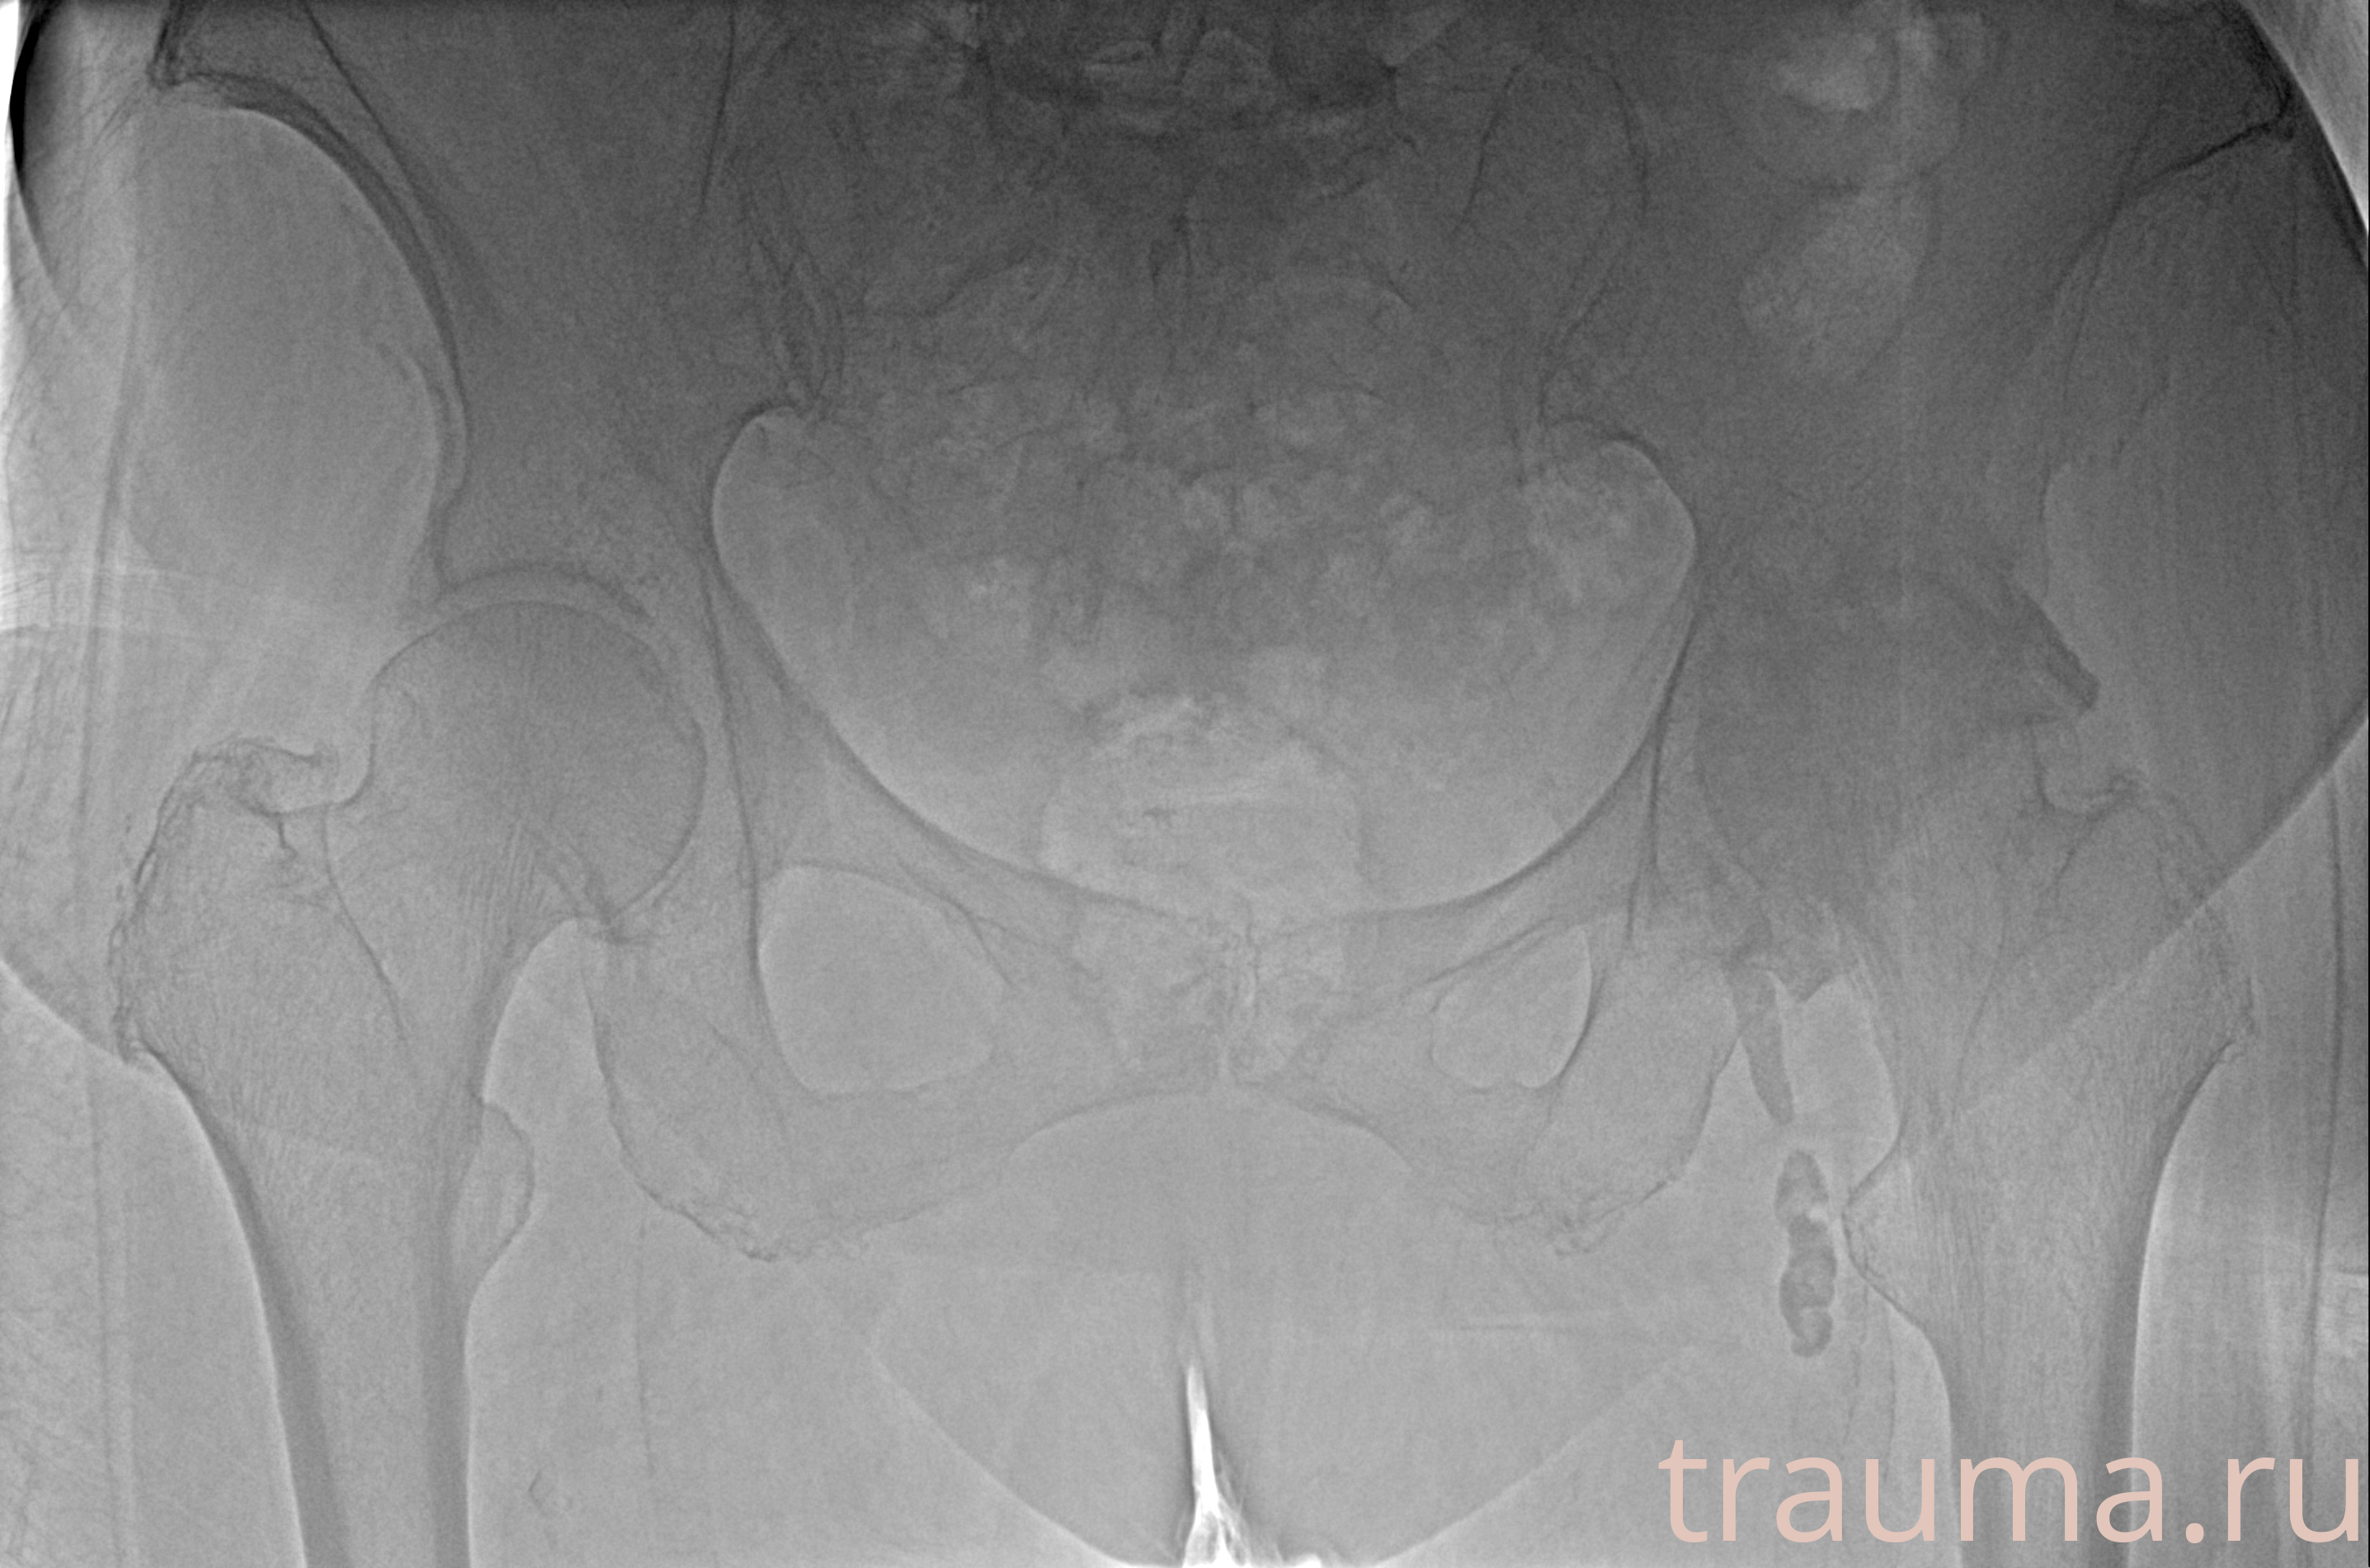

Рентгенограммы

Рентген на дому: по вашему адресу приезжает врач-рентгенолог, травматолог-ортопед с мобильным рентгеновским аппаратом, проводит диагностику травмы или заболевания, делает необходимые рентгенограммы, дает рекомендации по дальнейшему лечению. Получить качественные снимки в домашних условиях возможно благодаря уникальной методике, разработанной МосРентген Центром для института  Склифосовского